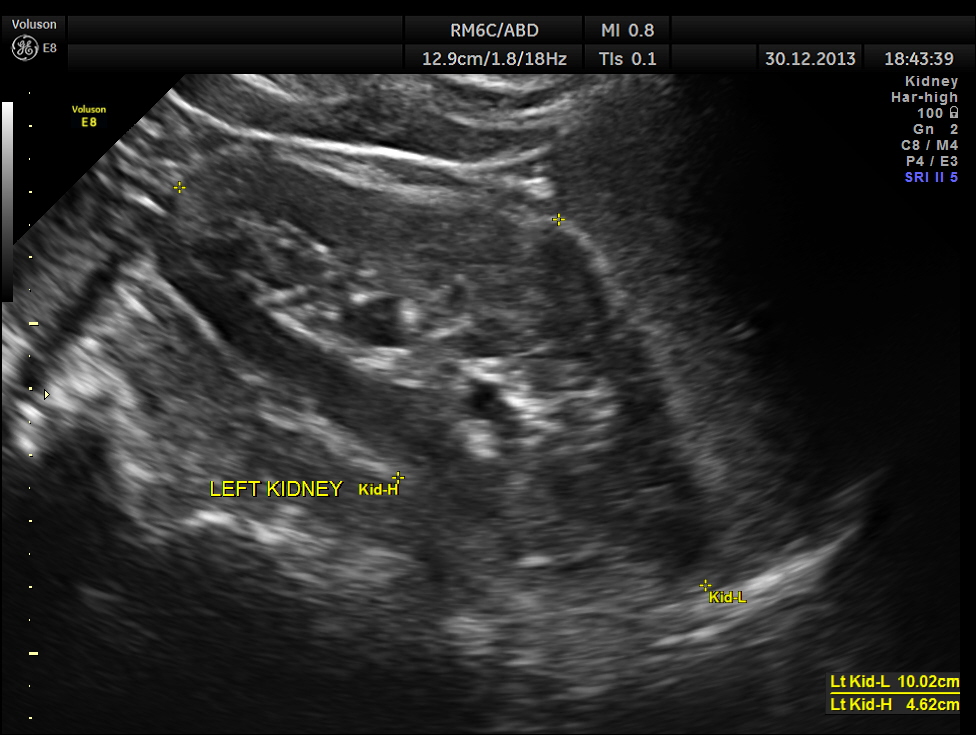

the kidneys were normal.